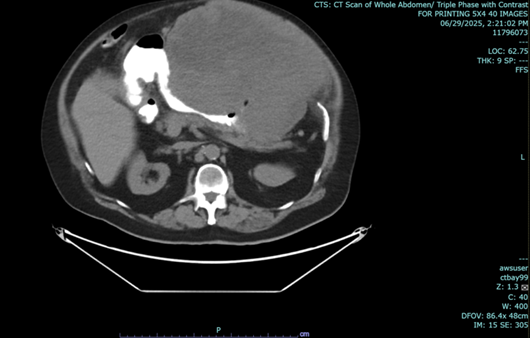

In the above latest admission, his abdominal CT Scan showed gaseous distention of stomach with ill-defined nodular thickening of posterior aspect of the body; the previously noted large lesion in stomach was not clearly demonstrated due to gaseous distended stomach.

Figure 2: a-c: September 17, 2025 Abdominal CT Scan showing previously noted large mass in stomach not clearly demonstrated due to gaseous content.